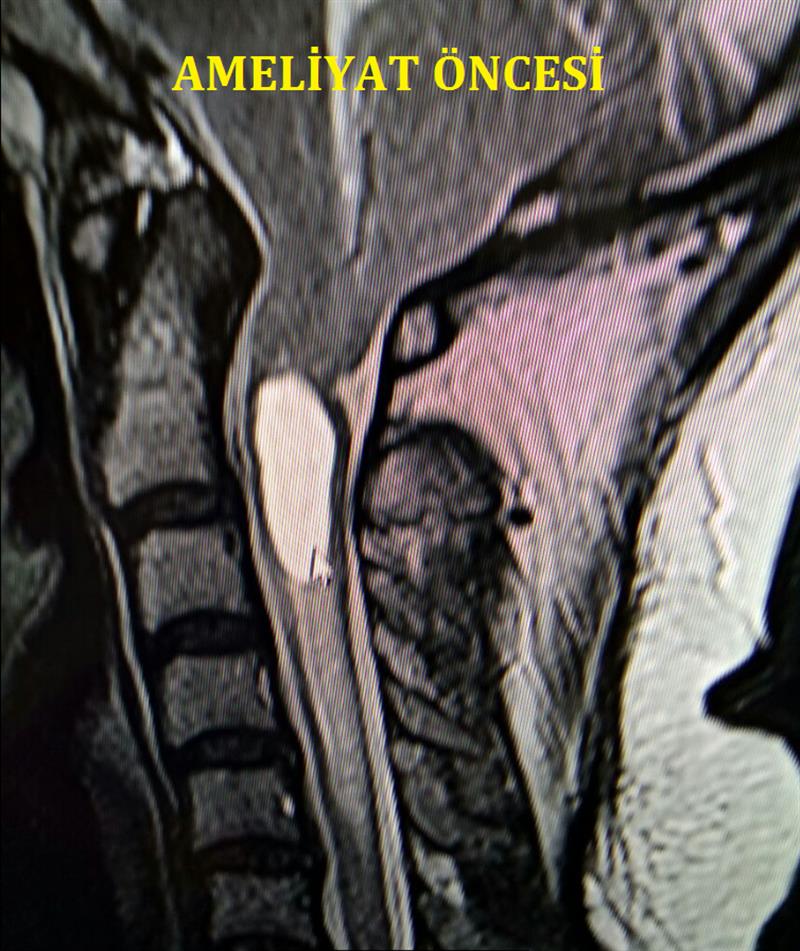

Bu malformasyonun incelemesinde günümüzün en iyi tetkik yöntemi Magnetik Rezonans Görüntülemedir (MRG). Servikal MRG incelemesinde bir veya her iki beyincik tonsillasının foramen magnumun altında uzanmasıdır.Ancak bu sarkma numerik olarak çok da anlamdı değildir. Çünkü beyincik sarmasındaki sebeb olaylar farklı olduğundan örneğin 3 mm lik bir sarkma bile beyincik sarkmasını şikayet verir hale getirebilirken veya 8 mm lik sarkma hiç bir zaman şikayet vermeyebilir. Bu tip anomalilerde beraberinde birlikte küçük posteriör fossa, platibazi, atlanto-oksipital asimilasyon veya baziler invaginasyon gibi anomaliler eşlik edebilir.Bu yüzden boyun bölgesisinin 3 boyutlu Bilgisayarlı Tomografi testleri ile bu anomalilerin bulunup bulunmadığı dikkatlice araştırılmalıdır.Beyin tomografi testinde beyincik ve foramen magnumun kemiksel anotomik detaylar incelenir. Bu inceleme Cerrahi stratejide oldukça önem arzetmektedir.Ayrıca beyin içerisinde BOS dolanımı için beyin BOS dinamiği gözden geçirilmelidir.. Arnold-Chiari malformasyonun % 50-60 ında hidro-sirengomyeli kaviteleri birlikte görülmektedir.

Sonuç olarak: Tip-1 beyincik sarkması bir doğumsal anomali olup oluşumunda bir mekanik blok sonrası sinir elamanları basısı ve BOS dolanımı engellenmesi söz konususdur. Genellikle genç erişkin yaşında değişik subjektif veya objektif şikayetleri vardır. Bu şikayetler arasında en sık olanları baş ağrısı,boyun ağrısı ve omuzlarda ağrı sıktır: Hastaların %60 ında beraberinde spinal omurilik içerisinde sirengomyelik kavitasyon bulunur. Teşhisde servikal MRG altın standart olup beyincik tonsillaları servikal spinal kanal içerisine yer değiştirmiştir. A- Chiari tip 1 in tedavisi cerrahidir.Cerrahi tedavide suboksipital dekompresyon, duraplasti en sık yapılanıdır. Eğer cerrah ameliyat esnasında ense bölgesindeki, varsa kemik,baskıları kaldırıırsa veya beyincik içerisisndeki BOS dolanımını engelleyen nedeni ortadan kaldırısa cerrahi tedavinin sonuçları mükemmeldir Böyle durumlarda beyincik sarkması şikayetlerin tama yakın iyileşmektedir. Eğer Beyincik sarkmasının nedeni ortadan kaldırılmazsa malesef şikayetlerde iyileşme beklenmmelidir. Böyle başarısısz durumları ayırıcı teşhiste bulanan hastalıkaları veya diğer beyincik hastalalıklarını gözden geçirilmelidir.